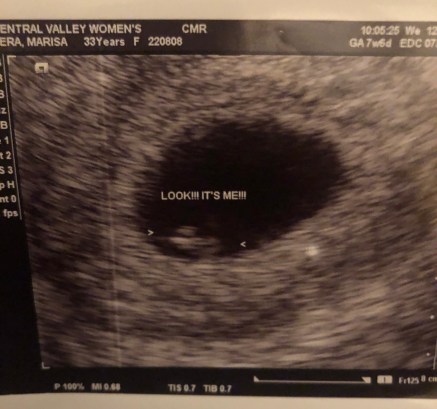

Today, for the third time I was told that our baby’s heart had stopped beating. Three fucking times. I am so angry. I am so devastated. I am so broken. As I’ve mentioned before, miscarriage was never on my radar until it happened to us. Now, it’s happened to me three times. Three times I had no cramping. Three times I had no bleeding. Three times I had no sign of miscarriage. I walked into my doctor’s office this morning, admittedly a little nervous but more than anything I was excited to get another positive ultrasound under my belt. I requested an early one (6 weeks) and the ultrasound tech said the size of the baby was textbook and I saw the fluttering heart on the screen. So, today I just wanted to get another positive visit to ease my mind and I honestly thought this baby was our little Christmas miracle. The baby to complete our family. I was wrong as so many women are.